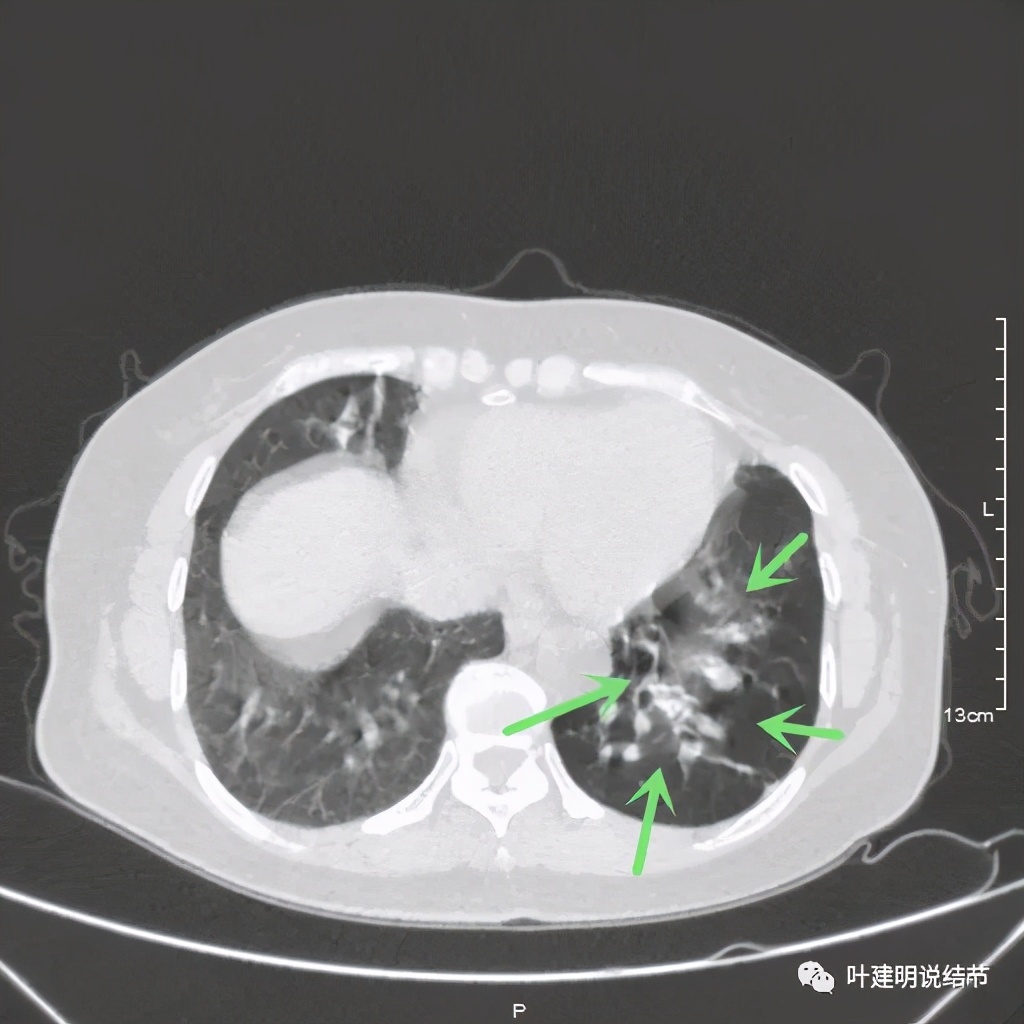

可见同样部位的左下结节已经较去年密度明显低了一些,说明有所吸收了!基本上已经只是磨玻璃密度了。那么其他病灶的情况呢?

也是有所变化,但病灶仍仍在,是异常的。最后这同图上还见到似乎也是实性伴小空腔的病灶(红色三角形标注处),是不是与之前的病灶有点像?

实性肺小结节的性质判断,一是看影像细节特征;二是看他处有没有类似病灶或病变;三是不太肯定是随访复查对比。这几点缺一不可,冒然过于积极手术,绝非最佳选择。网络问诊的病人的,经常有病友说,在某些大医院就诊咨询,大专家们经常会给似是而非的答案,告诉他们肺结节可能良性,也可能恶性,要病理化验才能确定。这样其实给病人仍是非常忐忑的心理负担,我们要用自己专业的判断,给他们尽量有倾向性的判断,帮助他们下决定随访抑或手术。我想,说清楚了,病人也会理解仅凭影像的判断达不到百分之百的。在避免过于积极干预的同时,也要避免耽误病情,而医生的不断努力能向更准确的术前诊断迈进!